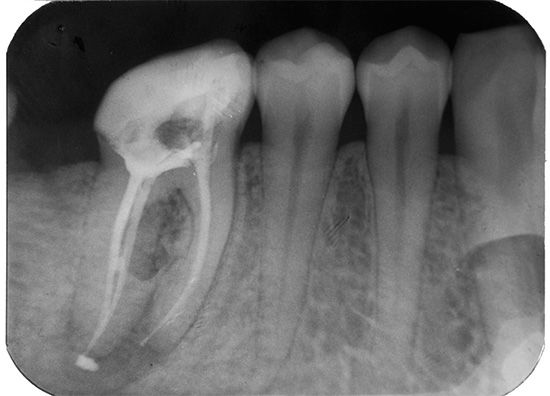

É possível diagnosticar tal complicação somente depois de estudar os dados de raios-X ou visográficos em um computador. Porém, a radiografia panorâmica de ambas as mandíbulas nem sempre permite um exame detalhado da parte superior das raízes dos dentes tratados e identifica o problema.

Se o comprimento do dente de trabalho for determinado incorretamente, não há ênfase apical, o pino de guta-percha não é dimensionado corretamente, o material é removido para a raiz do tecido circundante. Ao mesmo tempo, é possível observar no raio-x como a faixa branca do material de enchimento passa dentro da raiz, atinge seu ápice e continua. Mesmo uma pessoa que não é completamente avançada em odontologia pode diagnosticar facilmente o erro de um médico quando o alfinete de guta-percha se estende além da raiz em 4-5 milímetros ou mais.